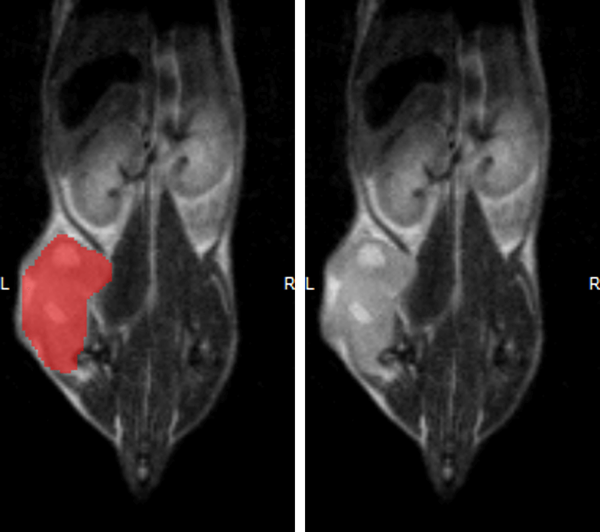

Hindlimb tumor growth: Monitoring the growth of xenograft tumor grown in the mouse hindlimb is identified with T2-weighted images. Segmentation of tumor region of interests (in red) on each tumor-containing slice allows accurate volume quantification.

Hindlimb tumor growth: Monitoring the growth of xenograft tumor grown in the mouse hindlimb is identified with T2-weighted images. Segmentation of tumor region of interests (in red) on each tumor-containing slice allows accurate volume quantification. Image Credit: Scintica Instrumentation Inc

Monitoring the growth of xenograft tumor grown in the mouse hindlimb is identified with T2-weighted images. Segmentation of tumor region of interests (in red) on each tumor-containing slice allows accurate volume quantification

Monitoring the growth of xenograft tumor grown in the mouse hindlimb is identified with T2-weighted images. Segmentation of tumor region of interests (in red) on each tumor-containing slice allows accurate volume quantification. Image Credit: Scintica Instrumentation Inc